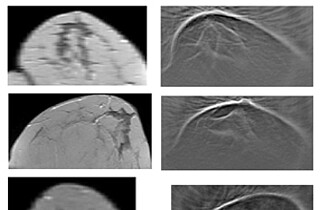

Forschenden des Instituts für Biomedizinische Technik (IBT) des KIT ist es gelungen, das ventrikuläre Fernfeld messtechnisch zu erfassen und in Echtzeit aus dem Signal zu entfernen. Das Forschungsteam hat einen Algorithmus für die diagnostisch wertvolleren unipolaren Elektrogramme entwickelt, bei dem sie die bei der Formerfassung des Vorhofs anfallenden Daten nutzen, um eine zeitlich-räumliche Verteilung des VFF zu erstellen. Diese Daten werden als Vorwissen genutzt, um für jede Position des Katheters den VFF-Anteil vorherzubestimmen und die unerwünschten Störungen zu unterdrücken.

Diese Messmethode bietet neben der räumlich klaren Zuordnung auch die VFF-Vorhersage in Echtzeit. Weiterhin wird das diagnostische Potenzial der unipolaren Signale nutzbar gemacht und eine genauere Bestimmung des zu abladierenden Gewebes ermöglicht. In Summe führt das Vorgehen zu einer schnelleren und präziseren Behandlung von Herzrhythmusstörungen und verspricht eine höhere Erfolgschance bei der Behandlung.